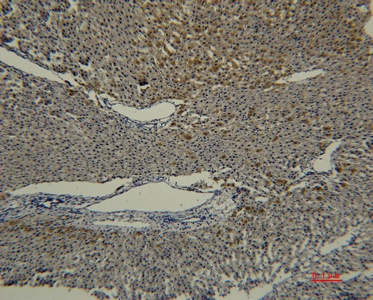

Fig. Immunohistochemical analysis of paraffin-embedded rat-liver using antibody diluted at 1:50.